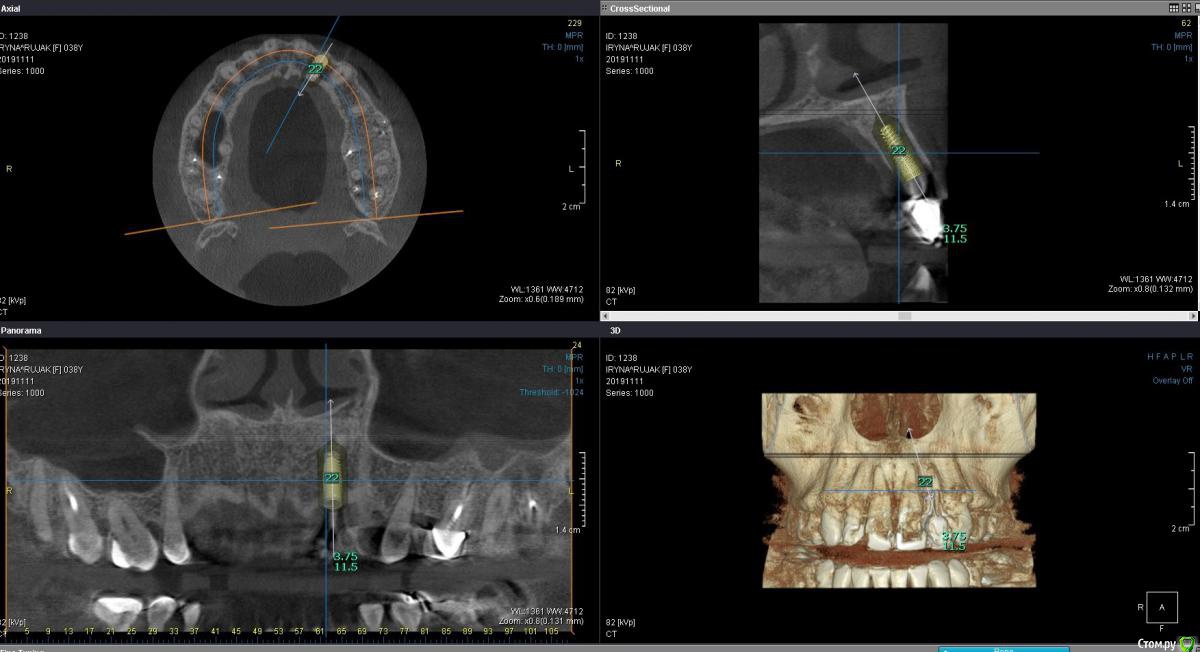

Пациентка 37 лет, не курит, соматически здорова. Частое выпадение ЛШКВ с коронкой. Диагностирована  фрактура вестибулярной стенки кореня зуба 22. Линия улыбки высокая. Биотип толстый.  Отсутствие вестибулярной пластинки, карман 8мм без ексудата.  Латеротрузия через 22.

Какая стратегия предпочтительней удаление корня 22, НКР, времянка понтик, потом имплантация с правельним наклоном. Или одномоментно с вестибулярным уклоном и в будущем  инд.абатмени+цементная фиксация.

2 вариант смело,через навигацию